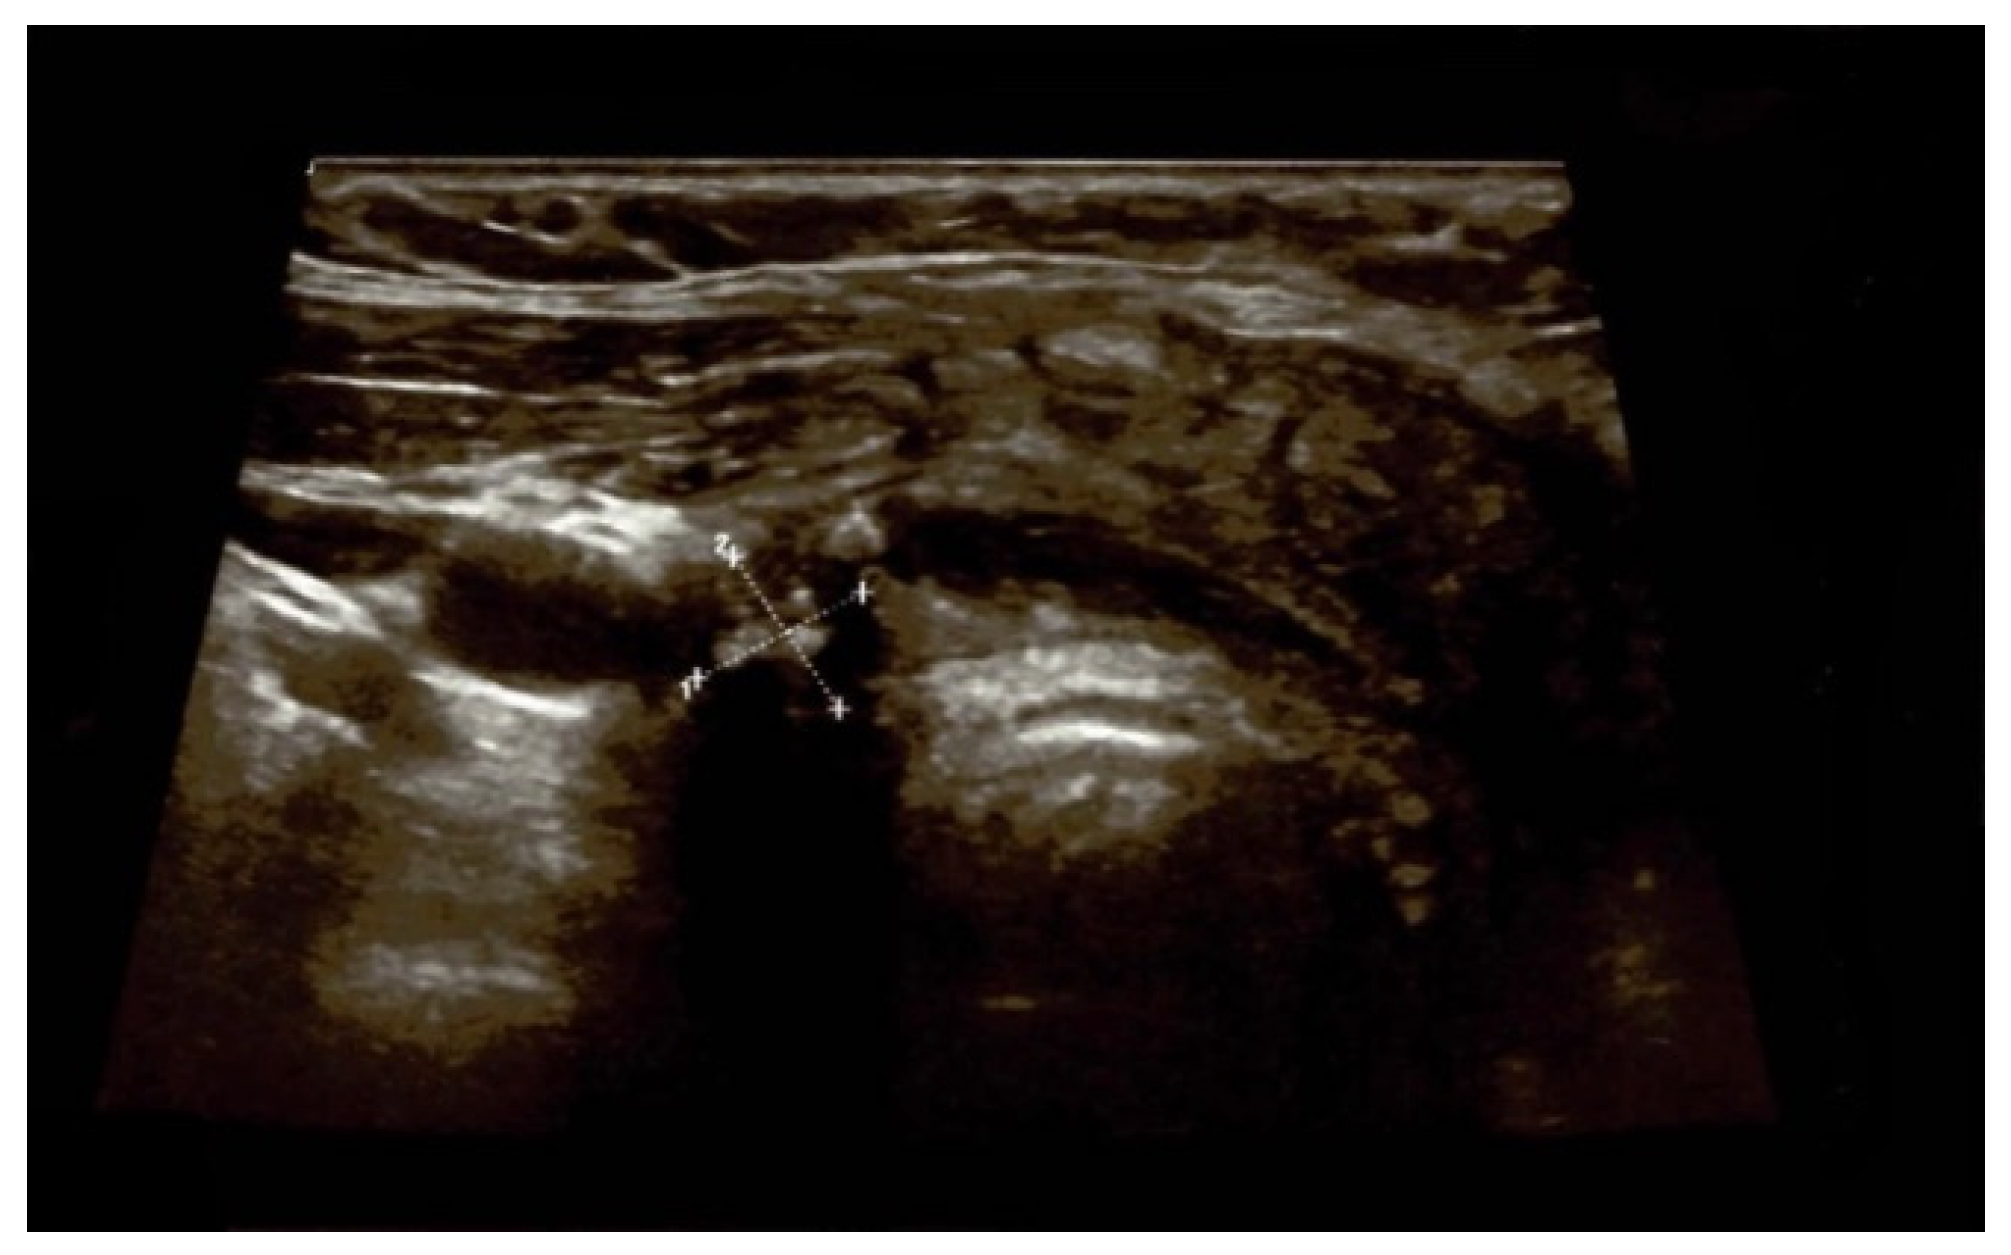

4.1.3. Post-Operatory Assessments

4.1.4. Redo Thyroidectomy